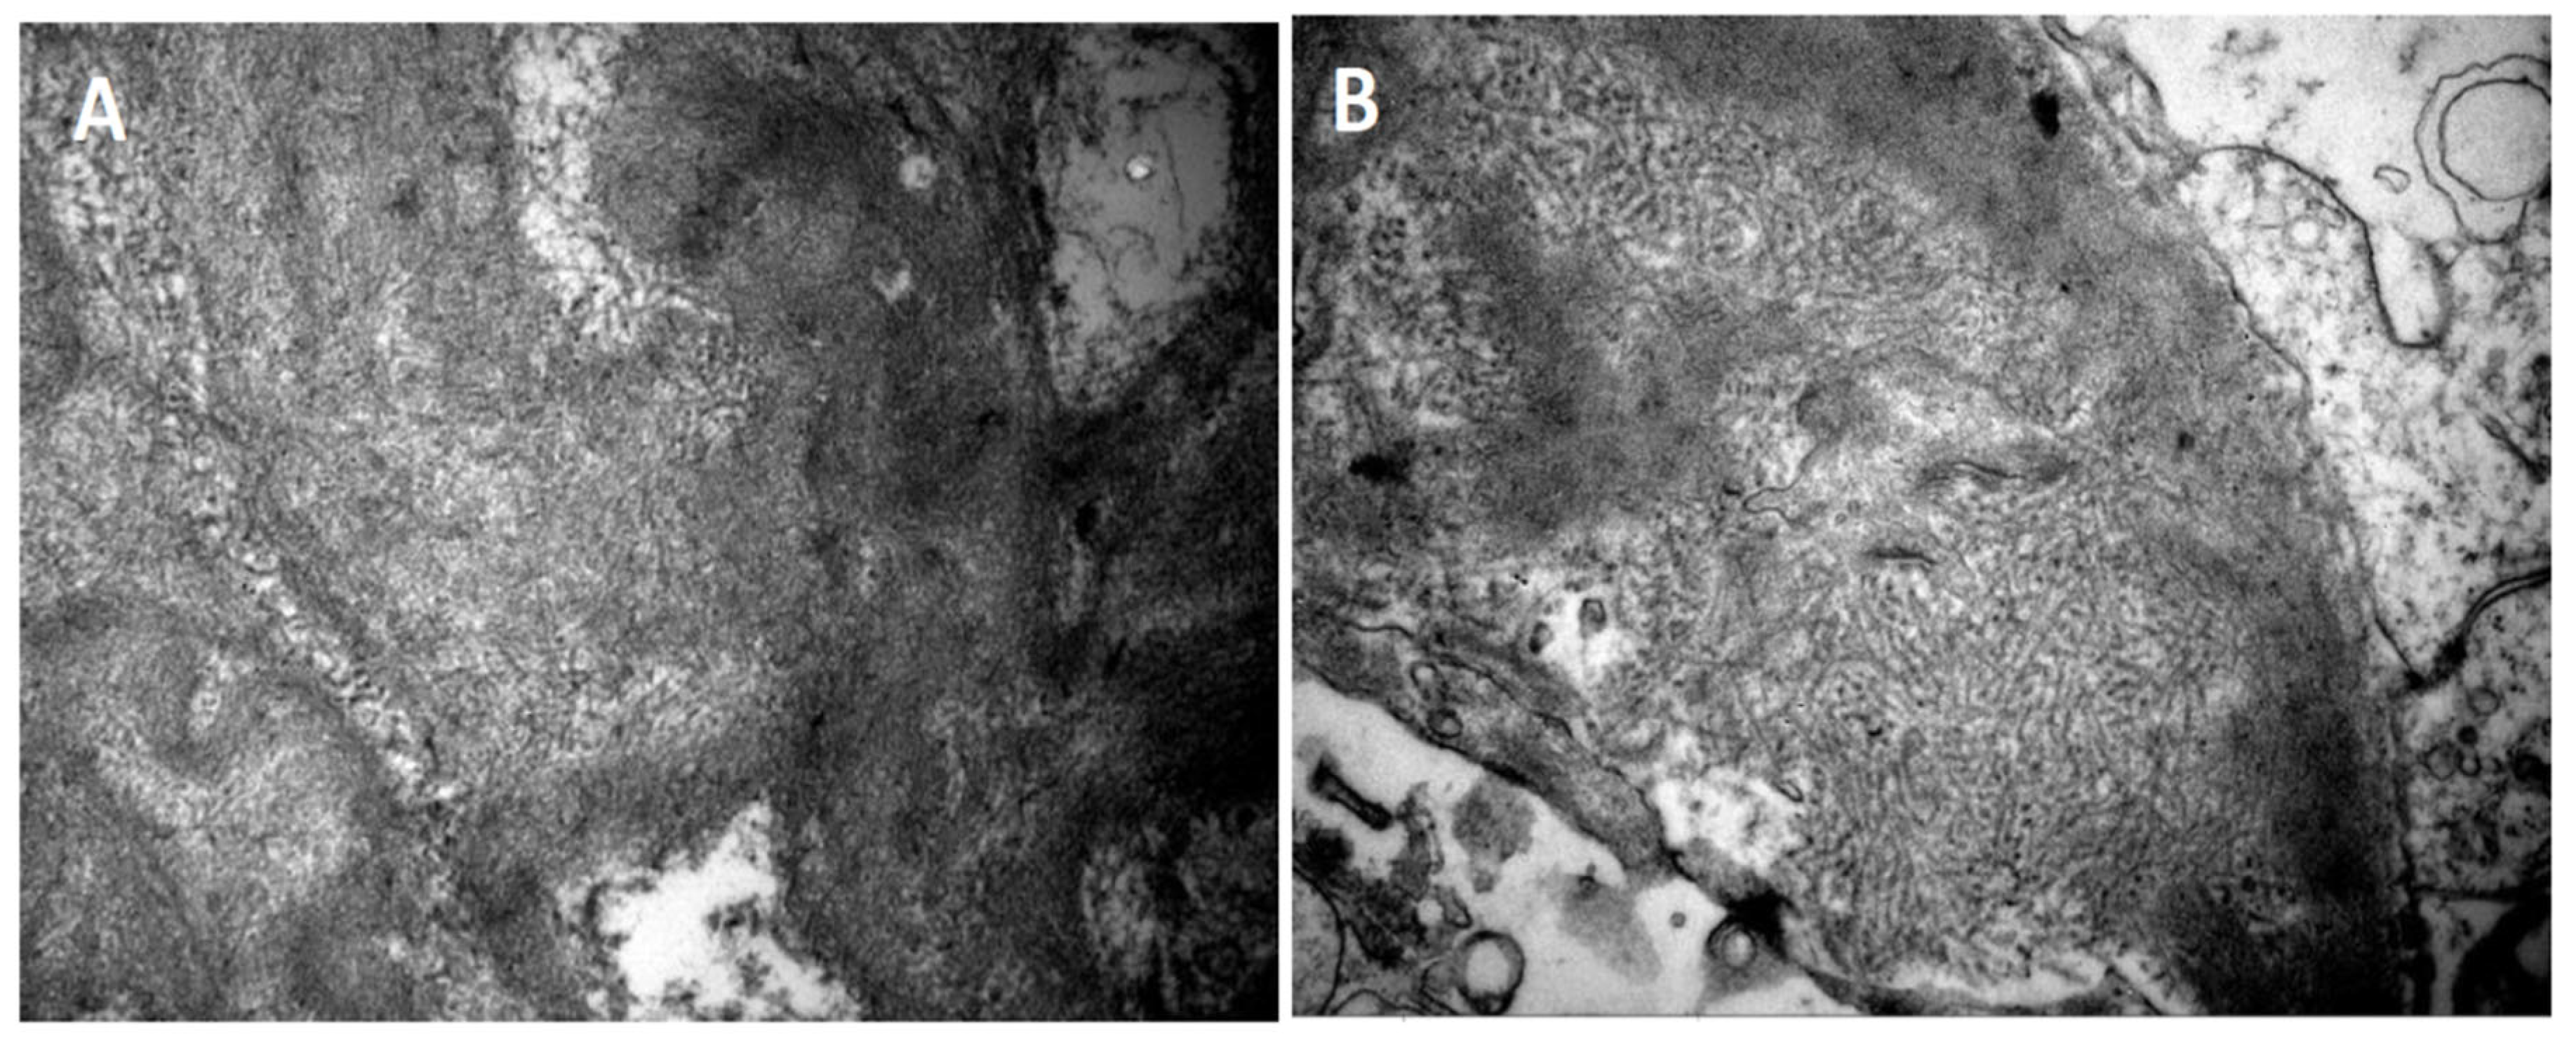

- Deposition of fibrils in the glomerulus by light electron microscopy. The fibrils must have the following characteristics:

- Random arrangement;

- Diameter of 14 to 24 nm;

- Deposition in the mesangium and the glomerular basement membrane.